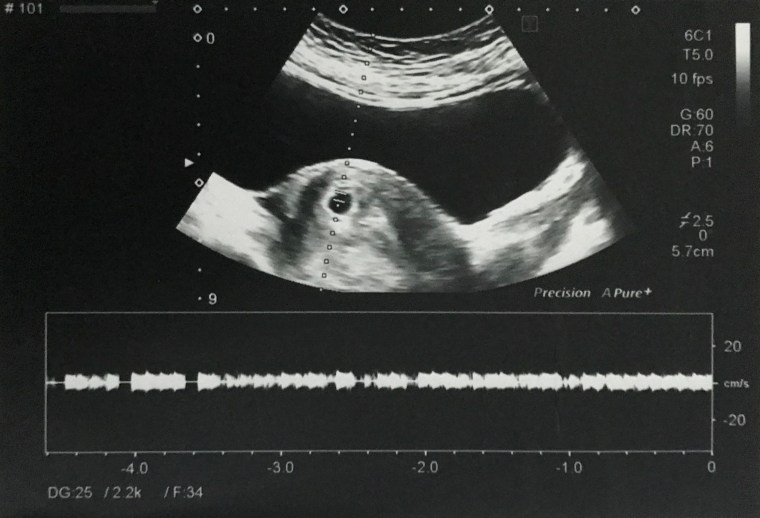

When I was on my 33rd week, I experienced light bleeding and pain on my lower abdomen. This prompted us to go to the hospital and have an ultrasound. I didn’t know that there were contractions that time and I might give birth any time. I was confined for 3 days and was put on bed rest until the end of June. I was given 2 shots of steroids as well in order to develop the lungs of our little one, just in case I gave birth that time.

Ultrasound at 33 weeks